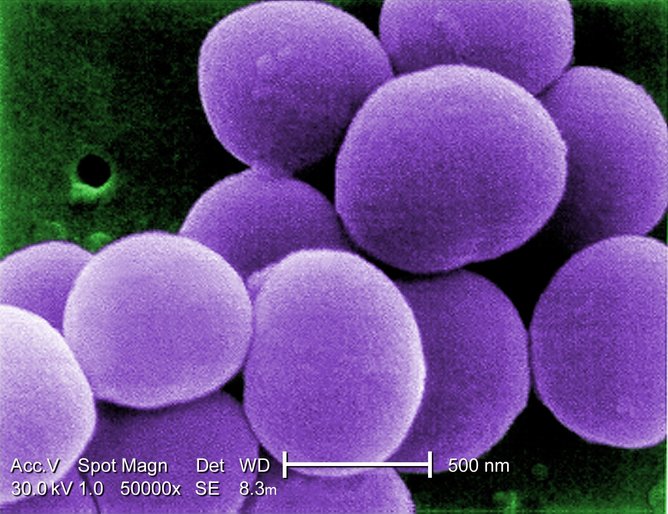

金黄色葡萄球菌一直困扰着研究者研究超级细菌引起致死感染的机制。(图片来源:Janice Haney Carr/wikimedia)

诸如MRSA(耐甲氧西林金黄色葡萄球菌)等臭名昭著的细菌被认为是“超级细菌”。这不仅是因为它们能够通过各种各样的毒力机制致我们于死地,还因为他们能够耐受许多抗生素。然而,对于大多数人来讲,定植在很多人皮肤及鼻道上的超级细菌所造成的负面影响微乎甚微。

然而,我们最新的研究表明,金黄色葡萄球菌(学名Staphylococcus aureus,MRSA简写中的SA)的情况恰恰相反。